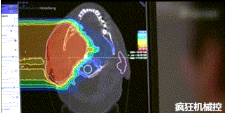

▲360°重離子治療一體機(jī)治療腫瘤

360°重離子治療一體可從任何角度用重離子(碳,氦,氧)和質(zhì)子(氫)照射腫瘤。此外,基于機(jī)器人的治療臺(tái)可以通過六種方式進(jìn)行調(diào)整。

光柵掃描被集成到360°重離子治療一體機(jī)中,這種極其精確的照射方法以毫米為單位掃描腫瘤,可以保護(hù)健康組織且只治療腫瘤區(qū)域。

特別是腫瘤在高度輻射敏感位置或者諸如視神經(jīng)附近的復(fù)雜位置,可以通過選擇最佳射束入射角來減小這些器官的損傷。